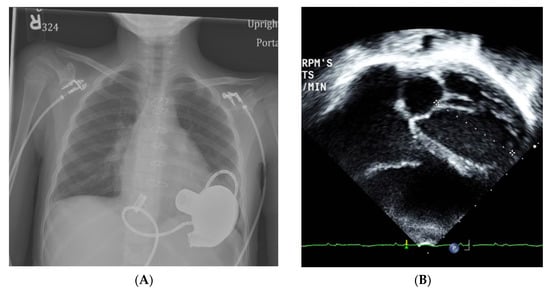

- Case 2: